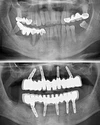

Implant Treatment